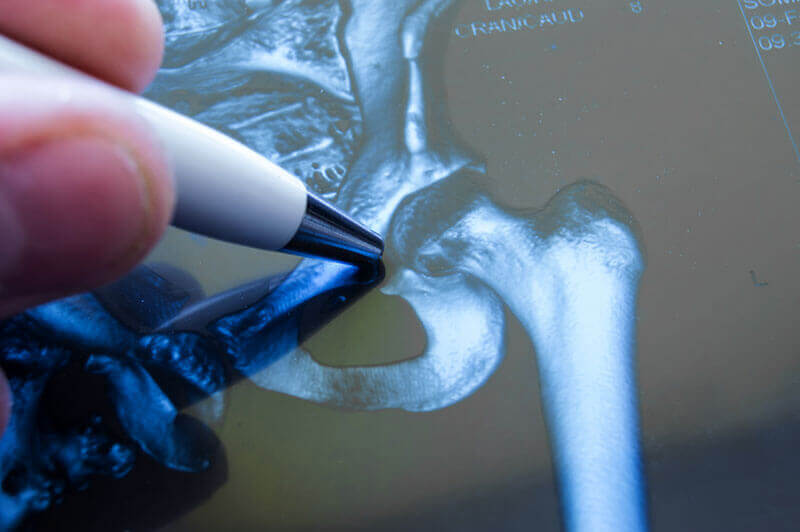

Diagnosticarea coxartrozei

Coxartroza poate fi diagnosticata de un medic practicant numai cu ajutorul radiografiilor. Examinarea ajuta la definirea gradului de dezvoltare a bolii si a etiologiei acesteia.Primul lucru de care trebuie sa tineti cont este calificarea medicului: este important pentru diagnosticarea bolilor. Destul de des, un specialist dezvolta planul de tratament al coloanei vertebrale uitand de examinarea articulatiilor soldului si pierzand astfel timp pretios.

- Examinarea cu raze X. Aceasta permite vizualizarea starii soldurilor si evidentierea simptomelor.

- Tomografia pe calculator sau imagistica prin rezonanta magnetica. Cel mai adesea, RMN-ul este preferat datorita absentei radiatiei X si a vizualizarii detaliate. Aparatul permite scanarea pe straturi, aflarea stadiului bolii si descoperirea acesteia in stadiile incipiente ale dezvoltarii.